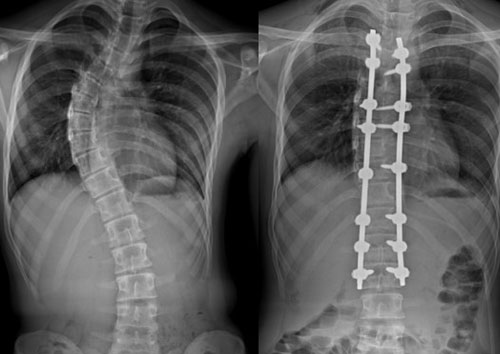

Scoliosis

Scoliosis is a condition where the spine curves sideways, forming an "S" or "C" shape. It can develop at any age but is most commonly seen in adolescents. There are several types of scoliosis, including idiopathic scoliosis (the most common form, with no known cause), congenital scoliosis (present at birth due to malformations of the spine), and neuromuscular scoliosis (associated with neurological or muscular conditions such as cerebral palsy or muscular dystrophy).

2. Surgical Treatment:

• Spinal Fusion Surgery: Recommended for severe curves (greater than 40-50 degrees) or if conservative treatments fail. The goal is to straighten and fuse the vertebrae to prevent further progression.

• Vertebral Body Tethering: A newer technique used in select cases to allow for continued spinal growth while correcting the curvature.